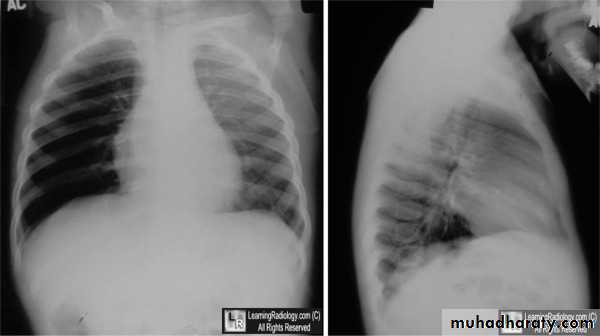

CXR : expiratory or lateral decubitus , reveal the presence of radiopaque objects and can also identify focal air trapping.

Expiratory chest radiograph in a 12-month-old boy with a 2-month history of wheezing demonstrates continued hyperlucency and hyperexpansion of the right hemithorax.